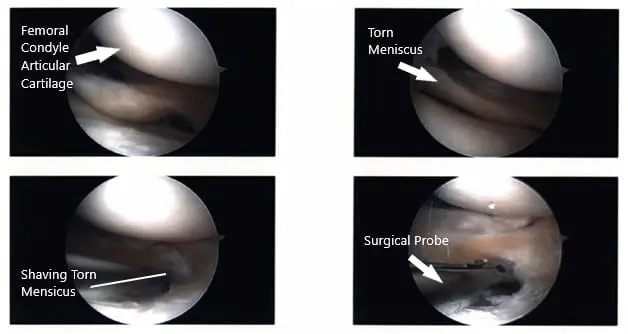

Intraoperative Arthroscopic images of the left knee.

Examination of the tibiofemoral joint showed a tear of the medial margin of lateral meniscus, which was cleaned using a shaver and up biters. There was no tear in the medial meniscus. There was large popliteal hiatus with the possible tear going into the posterior horn of the lateral meniscus, which was incomplete.

A thorough examination was done and the debridement was done. The decision was done not to repair it at present because it seemed to be an extension of the popliteal hiatus.